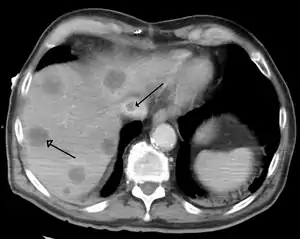

| .jpg.webp) | |

| A gross pathology specimen of liver metastases caused by pancreatic cancer | |